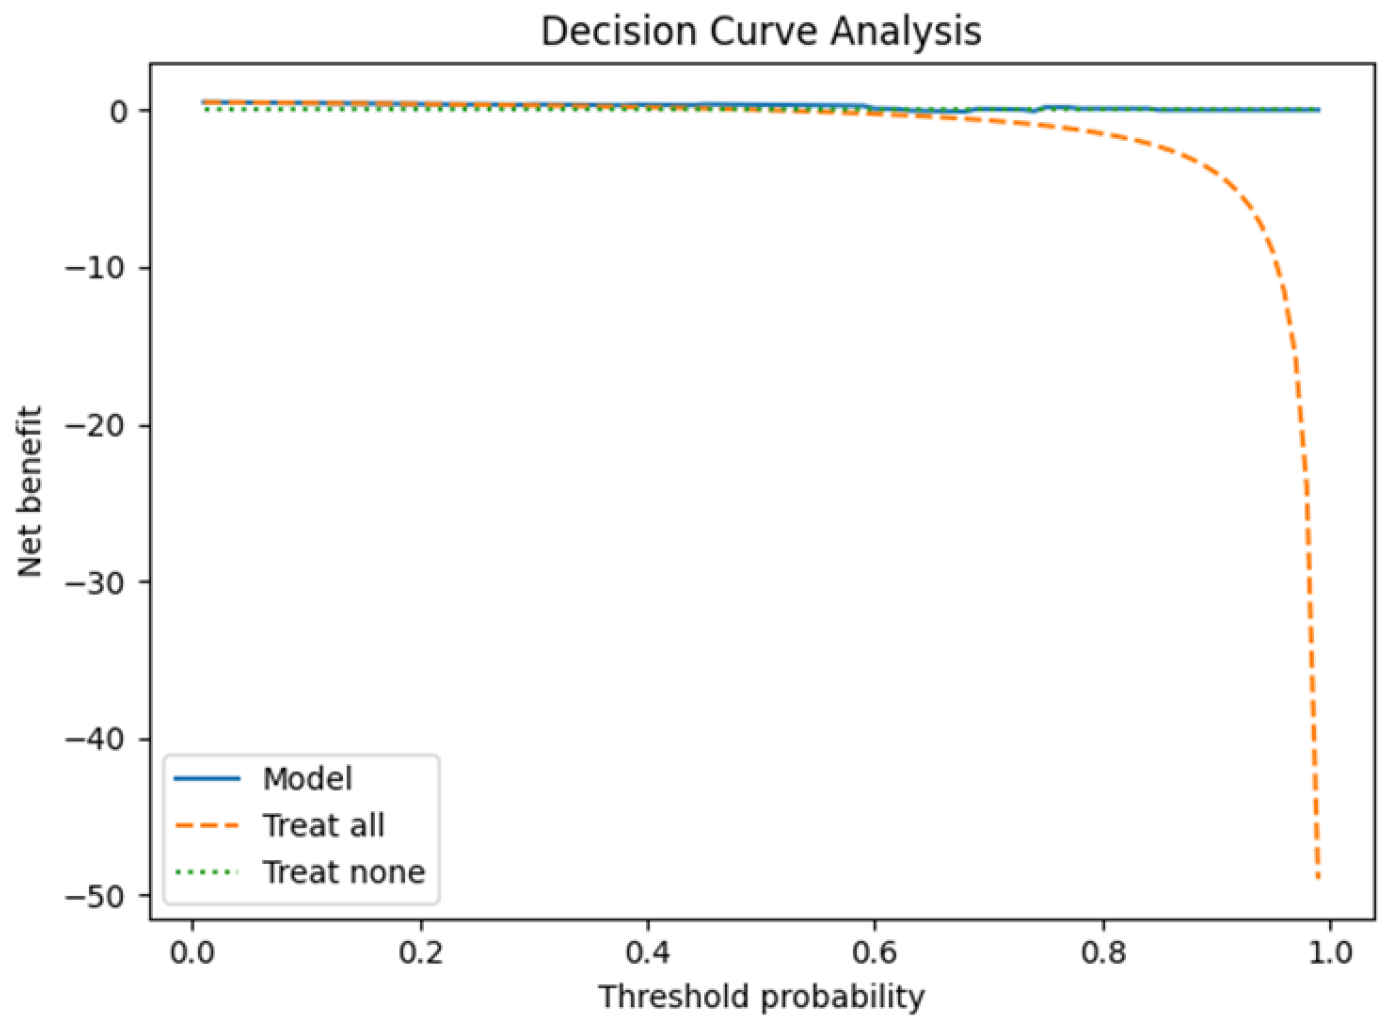

3.1. Leave-One-Patient-Out Cross-Validation (LOPO-CV)

4.2. SVM Classification and Model Robustness